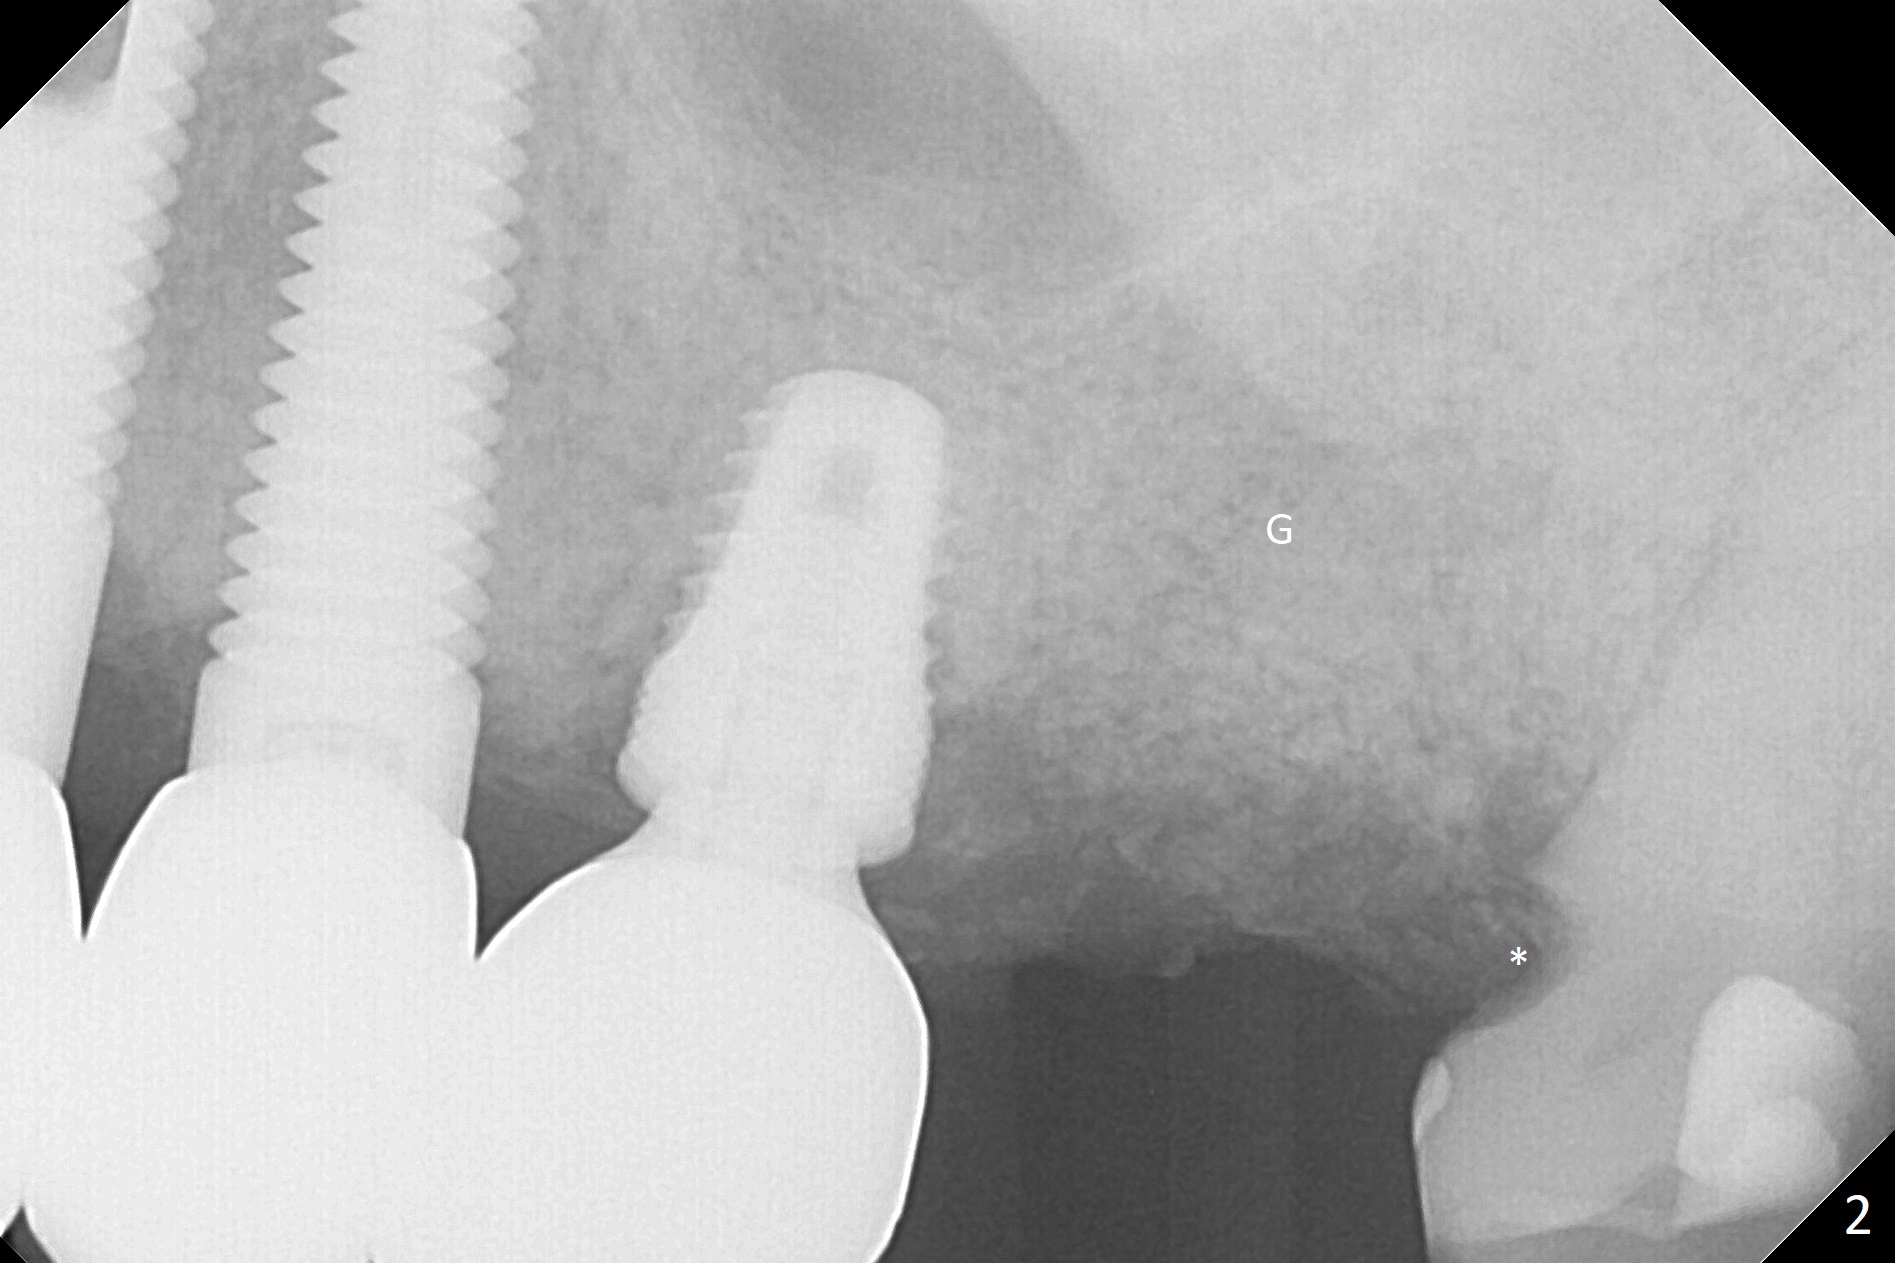

The 7x14 mm implant at #15 of a 89-year-old man is found to be loose ~ 1 year post cementation (Fig.1). After implant removal and debridement, bone graft is placed (Fig.2 G); the mesiocervical caries of the 3rd molar is removed, but not filled (*). With collagen membrane fixed with Chromic gut suture (Fig.3), setting acrylic is applied in the edentulous area, including the mesiocervical cavitation of the 3rd molar (Fig.4) for further retention. Bone graft gets lost following socket preservation at #31 with periodontal dressing. When the bone graft matures, a new implant (Fig.6 green) will get primary stability from the native bone, i.e., coronal to the sinus floor (Fig.5 F). The acrylic dressing (Fig.7 A) with a portion locking to the undercut of the neighboring crown (*) remains in place 5 weeks postop. When the dressing is cut off, the bone graft is exposed with odor (Fig.8,9 *). Periodontal dressing is applied. The distolingual portion of it gets lost due to brushing a day later. When he returns, the dressing is removed (Fig.10). It appears that the growing in gingival margin is pushing the bone graft out. A moment later after just a few rounds of swallowing, more graft is lost (Fig.11). We would love to leave the wound open, but the senior citizen complains of air leaking and requests reapplication of periodontal dressing. The bone graft is almost gone when the 2nd periodontal dressing is removed nearly 2 months postop (Fig.12). The tooth sensitivity disappears when MO caries is taken care of. The socket has a dimple 5 months postop (Fig.13), although it is filled with bone graft (Fig.14). Due to low bone density (~500 HU), sinus lift is required for implant stability with PRF (Fig.15). In fact the lab chooses not to do sinus lift.